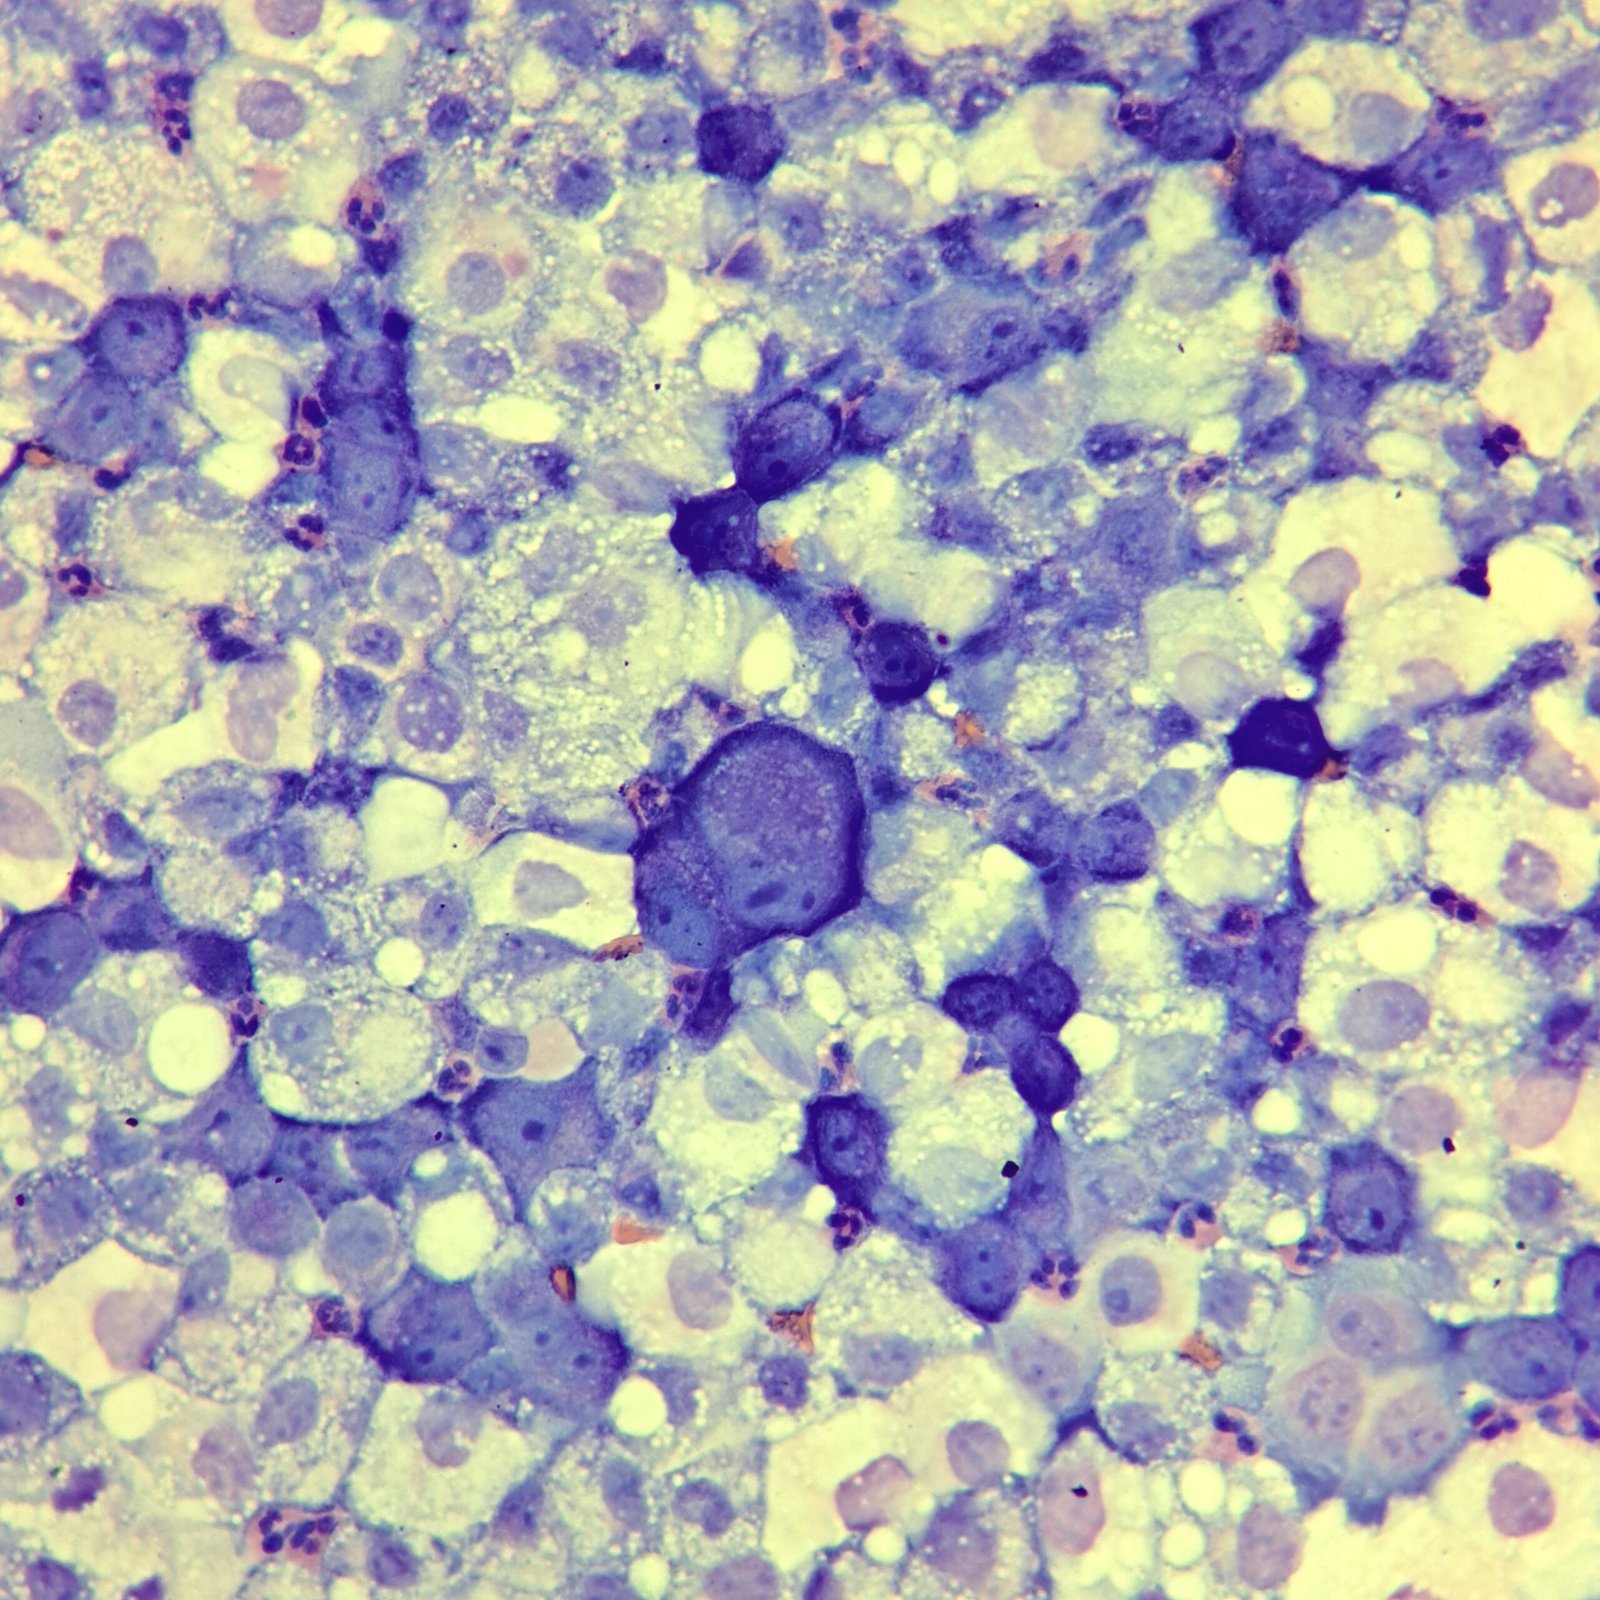

Mesothelial cells are described as having a “fried egg” appearance. They have a round to oval nucleus with smooth borders and evenly distributed chromatin. Nucleloli are usually present. Mesothelial cells may also be multinucleated.

Cells may be seen in clumps, but “windows” between cells still allows for individual counting.

Both malignant cells and mesothelial cells can clump together. However, malignant cells will not have the windows between cells.